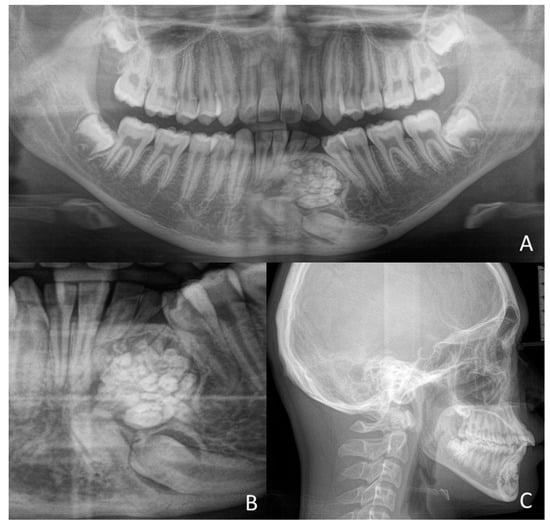

1.1. Case Number 1